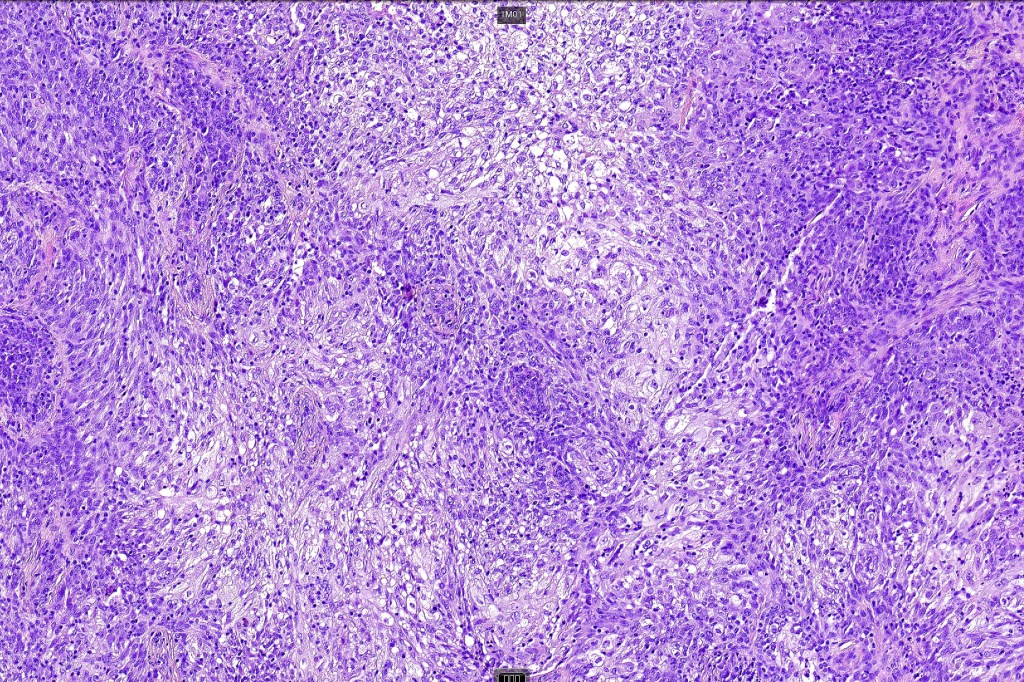

Histological features

•Biphasic tumor combining squamous cell carcinoma and adenocarcinoma; the latter showing ductal and glandular differentiation

•Variable pleomorphism & mitotic activity but can be marked